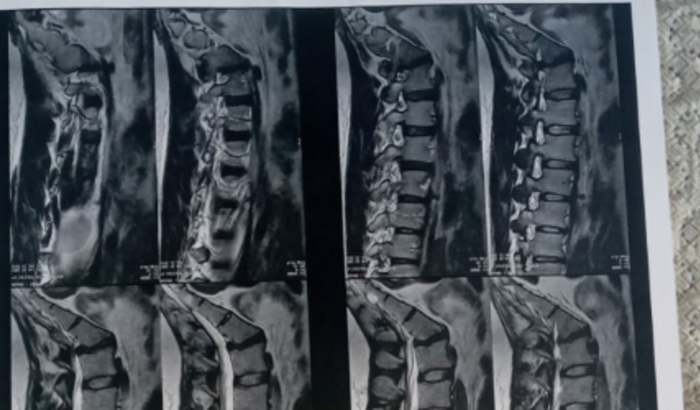

Meu nome é Mirian Costa Terleski, sou casada, tenho 35 anos, tenho dois filhos. Nascida e crescida em Sete Quedas, hje venho em busca de ajuda para realizar minha cirurgia de coluna, a 6 meses estou buscando tratamento pelo SUS, porém os pedidos de cirurgia sempre negado. No momento estou praticamente acamada, nem dentro de casa consigo caminhar e nem fazer coisas básicas, como cozinhar. Meu esposo é diarista, só ganha quando tem serviço e ñ chove.

_ Eu trabalhava em loja de roupas, cuidava da limpeza da casa, para ajudar nas despesas de casa. Hje estou impossibilitada de fazer o mesmo. Por isso venho através deste pedir ajuda, minha cirurgia custa 48.00,00, (mil) sem as depesas de internação, anestesista, e risco cirúrgico.